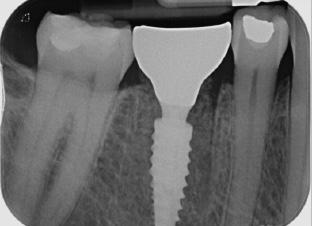

Synergy, as defined by the Cambridge Dictionary, is ‘the combined power of a group of things when they are working together that is greater than the total power achieved by each working separately’. When carrying out surgical procedures it is important that you use equipment solutions developed to offer a synergistic approach to your surgical processes. The equipment and instruments used should work in harmony to allow you to provide top quality treatment.

When it comes to synergy in dental implant procedures, such an approach often enables dental professionals to achieve better accuracy during the surgical phase. For instance, guided implant surgery utilises computer-generated surgical guides to enhance the precision of implant placement. By combining 3D imaging technology with specialised surgical instruments, dental clinicians are able to carefully plan the position, angle, and depth of the dental implant prior to the actual surgery. This collaborative effort between advanced imaging software and specialised instruments ensures that the implant is placed precisely in the desired location, leading to better aesthetic outcomes and increased patient satisfaction.

Seamless integration

Another advantage of instrument synergy in dental implant procedures is the reduced risk of surgical complications. Using specially designed surgical instrument and handpieces, allow dentists to ensure that they have everything necessary and readily available during a procedure. This allows the dental team to work efficiently and

effectively. The benefits of using compatible handpieces and equipment ensures that they can be seamlessly integrated into the surgical workflow, further reducing the time required for the procedure.

Seamless integration of instruments in dental implant procedures can also improve patient comfort and reduce recovery time. Advanced technology, such as piezoelectric instruments using ultrasound technology, offers precise and controlled cutting of bone, minimising trauma to the surrounding tissues. This means that patients experience less pain, swelling and bruising post-surgery, leading to a quicker and more comfortable recovery. Additionally, the combined use of specialised instruments, such as tissue punches and implant placement tools, allows for minimally invasive techniques that preserve the integrity of soft tissues. By reducing damage to the surrounding structures, patients experience less post-operative discomfort and achieve quicker healing.

clinical toolkit. Utilising the Piezomed improves procedure outcomes and results for patients as it is gentle on soft tissue ensuring reduced patient discomfort and quicker healing. For those placing implants measurement of osseointegration is ideal as it allows them to monitor the dental implants to inform loading decisions and ensure success. The Osstell Beacon from W&H, gives dental professionals peace of mind as they can measure and evaluate the stability of the implant ensuring full osseointegration, helping to reduce treatment times and avoid rejection in high-risk patients.

Working with equipment and instruments from top quality suppliers like W&H, who offer a highly synergistic approach based on many years of research, development and surgical know-how, allows for the best possible treatment outcomes. The Piezomed provides dental professionals with the benefits of innovative piezosurgery. By using the high-quality system, clinicians can remove only the targeted bone with precision, leaving the surrounding soft tissue and bone undamaged. The Piezomed module integrates seamlessly with the Implantmed Plus surgical unit, this flexibility between the Implantmed with surgical handpieces and the Piezomed creates a superior workflow driven solution for oral surgery, guiding the clinician through the cycle from implementation to evaluation. With W&H’s synergistic approach, which includes the use of the Implantmed, with the range of surgical handpieces, alongside the Piezomed the dentist benefits from an incredibly versatile

Overall, a synergistic solution to dental implant procedures offers numerous advantages that enhance the overall success of these procedures. Patient comfort is improved through the use of advanced instruments that minimise trauma and promote faster healing. With these advantages in mind, it becomes clear that dental implant procedures require wellthought through planning and the correct equipment. This helps to develop a solution which allows the clinician to provide high quality treatment enabling them to deliver patients with effective, efficient, and longlasting solutions for missing teeth.